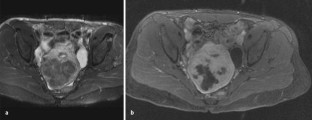

Abb. 1a,b

Abb. 5a,b

Abb. 7a–c